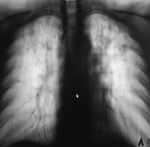

Контроль после "флюшки".

Туберкулёз.

Пост 46: по обзорке диссеминированный поставил бы.

Контроль после "флюшки"